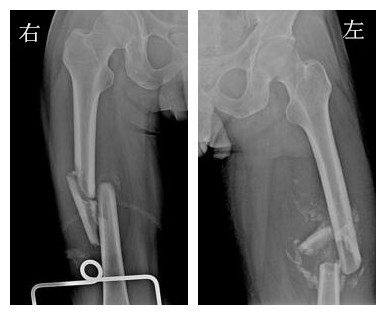

完善术前准备,广东三九脑科医院骨科王延斌主任及其团队在全麻下先后为患者进行“右侧股骨中段闭合性粉碎性骨折切开复位钢板内固定术”和 “左侧股骨中段陈旧性粉碎性骨折切开复位钢板内固定术”。

▲术后DR 双侧股骨骨折手术内固定位置良好